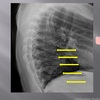

Lateral thoracic view

A

transverse process of c2-c7

LATERAL THORACIC LANDMARKS lateral thoracic view

disc spaces

108

endplate tips